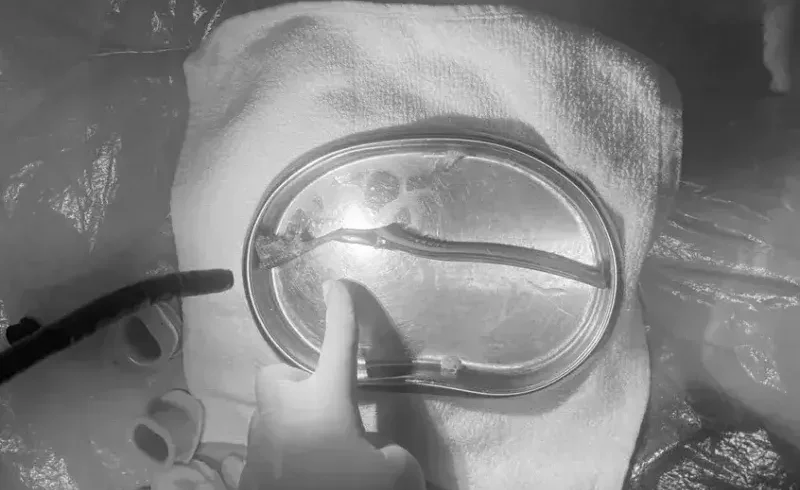

Ekip nội soi cuối cùng đã gắp thành công được dị vật là một chiếc bàn chải đánh răng nguyên chiếc dài thân phình vị đến hang vị dạ dày, dị vật dài khoảng 20cm.

- Hình bìa: Chiếc bàn chải đánh răng dài 20cm được gắp ra ngoài thành công.